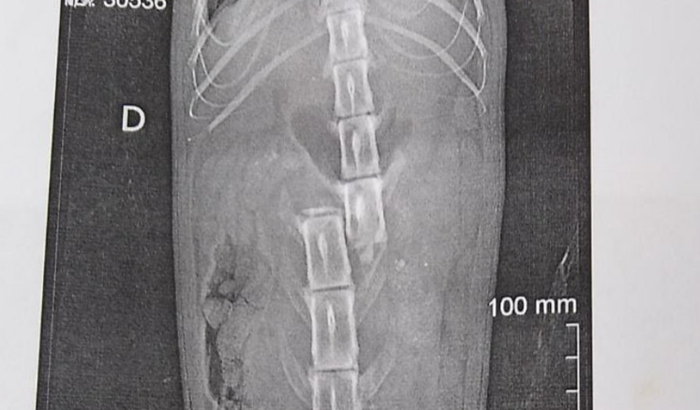

Sou o Sérgio e criei essa vaquinha, pois preciso arrecadar R$ 7.000,00 para fazer uma cirurgia de coluna, pagar as diárias da internação e comprar remédios para esse gato que encontrei em Taboão da Serra às 4 da manhã do 14/03/2023….se encontra internado aguardando pela cirurgia.